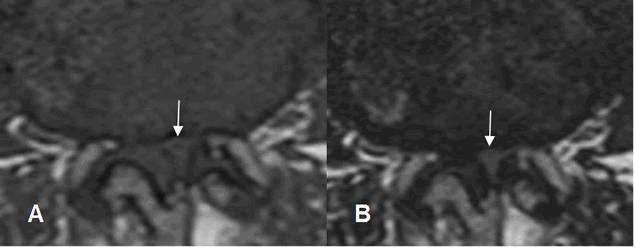

Fig 50. Acondroplasia.

A: RM axial y B: RM sagital en T2. Disminución en la amplitud del canal de origen congénito, con discos, ligamentos y facetas articulares normales.